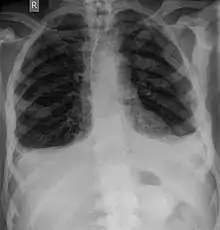

Rayons X

Pour le diagnostic initial, la radio X classique a une importance centrale. L'indication pour des projections sur deux plans est toujours donnée en cas de soupçon de tumeur osseuse[87]. Les métastases ostéolytiques sont caractérisées par une perte de densité osseuse. Ceci se reconnaît sur la radio par un noircissement plus élevé, en raison de la plus grande transparence aux rayons X. Inversement, les métastases ostéocondensantes présentent à cause de la plus grande densité osseuse un noircissement inférieur. Les métastases ostéolytiques sur la colonne vertébrale sont nettement plus difficiles à reconnaître : seulement quand environ 50 % de la densité totale de l'os a disparu[87].